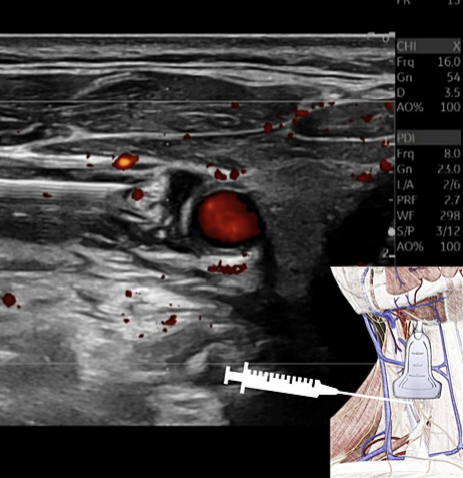

초음파 가이드 미주신경 자극술은**

미주신경에 다이렉트로 주사 치료하는 방식이라

상대적으로 간편하고 치료시간도 짧죠.

해당 연구자는 딱딱하게 굳은 목 조직에

눌려있는 미주신경을 초음파로 찾았습니다.

그리고 '5프로 포도당 용액'으로

신경 압박을 풀어주는 주사를 놓았습니다.

우리 몸의 삼투압과 유사한 5% 포도당을 주사해서

신경 주변 염증을 가라앉히고

에너지를 공급해 재생을 촉진해주죠.

초음파로 보면서 혈자리에 정확하게

약침을 주사하는데요.

인영혈 주변에는

미주신경 뿐만 아니라

천경신경총(Superficial cervical nerve plexus),

부신경, 횡격막 신경,

경정맥, 경동맥 등

다양한 신경과 혈관이 있습니다.

약물 볼륨으로 천천히 공간을 벌리면서정확한 타겟을 향해 진입합니다.

한 겹 한 겹

척추 앞 근막(Prevertebral Fascia)을 벗겨내면서

초음파 약침을 시술합니다.**